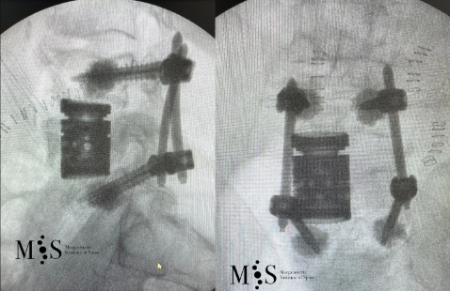

Caso clínico de una resección (corpectomía) y reconstrucción vertebral lumbar en una fractura estallido de nivel L4.

Resección (corpectomía) y reconstrucción vertebral de fracturas vertebrales complejas y conminutas

En los casos de las fracturas más graves, las fracturas conminutas y fracturas estallido, pueden conllevar que un fragmento del cuerpo vertebral se haya desplazado hacia el canal medular, provocando una compresión de las estructuras neurológicas (estenosis del canal medular).

En los casos en los que existe un compromiso neurológico se debe proceder a la resección parcial o total del cuerpo vertebral fracturado (corpectomía) y su posterior reconstrucción mediante una caja somática expandible. Se suele completar la reconstrucción mediante una artrodesis percutánea instrumentada y cementada de los niveles adyacentes a la fractura. La resección (corpectomía) permite extraer el fragmento de la vértebra que se encuentra en el canal medular y liberar las estructuras neurológicas afectadas. La reconstrucción mediante una caja somática permite descargar la carga del paciente sobre la fractura y quitar el dolor que ésta le provoca al paciente.